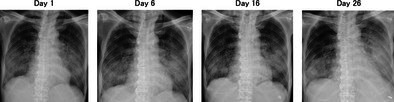

免疫检查点抑制剂(ICIs)是肺癌的基本治疗方法,但其在同种异体造血干细胞移植(alloo - hsct)后的安全性尚不清楚。我们报告一例66岁的男性,因急性淋巴细胞白血病而接受脐带血移植,后来发展为肺腺癌。开始了派姆单抗单药治疗,但患者出现了严重的类固醇难治性免疫相关肺炎,导致治疗开始56天后死亡。鉴于既往HSCT的肺癌患者使用ICI的报道很少,本病例强调了关键的安全性考虑。

Immune checkpoint inhibitors (ICIs) are essential treatments for lung cancer, but their safety following allogeneic haematopoietic stem cell transplantation (allo-HSCT) remains unclear. We report a case of a 66-year-old man who underwent umbilical cord blood transplantation for acute lymphoblastic leukaemia and later developed lung adenocarcinoma. Pembrolizumab monotherapy was initiated, but the patient developed severe steroid-refractory immune-related pneumonitis, leading to mortality 56 days after treatment initiation. Given the scarcity of reports on ICI use in lung cancer patients with prior HSCT, this case highlights critical safety considerations.